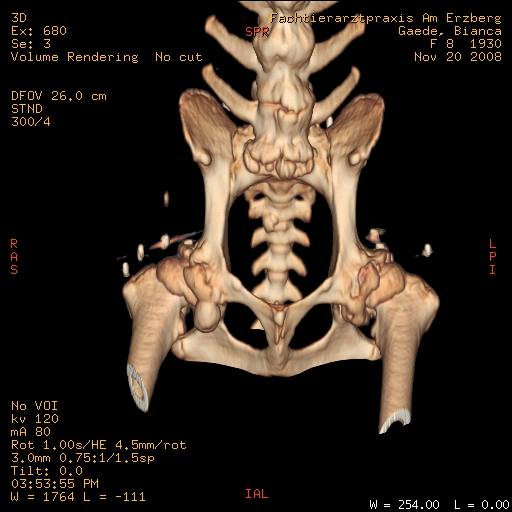

Bezüglich des CT, da ist einfach der große Vorteil, dass man auch Probleme der Knochen sehen kann, die eventuell zu klein sind oder nicht genau genug auf dem Röntgenbild.

Mal als Vergleich